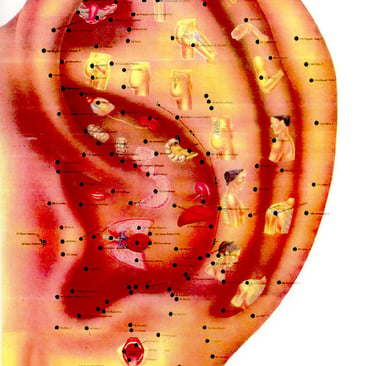

Libros de acupuntura y MTC

Galería

Momentos capturados de la medicina tradicional china en acción